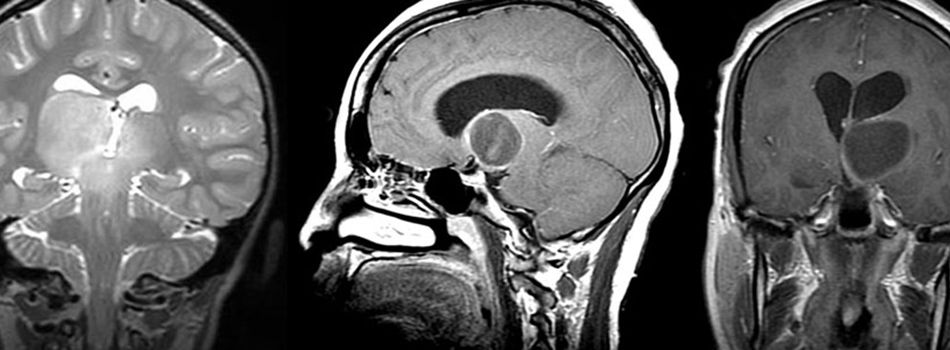

例如德国汉诺威国际神经外科研究所(INI)神经外科教授巴特朗菲(Helmut Bertalanffy),他在一份研究报告中表示,其曾治疗的患者中有一名33岁的孕妇,就诊前具有严重的头痛、平衡感失调和记忆力缺失的症状。在为这名孕妇进行磁共振图像(MRI)检查时发现占据两侧脑室后部的毛细胞型星形细胞瘤。

教授在这名孕妇平稳分娩后,为其经胼胝体前入路进行手术,并完全切除了肿瘤。术后,这名患者除出现短暂的轻度记忆缺失之外,后续并没有出现任何神经或认知上的缺陷,并且教授通过随访MRI对照,排除了肿瘤的复发。